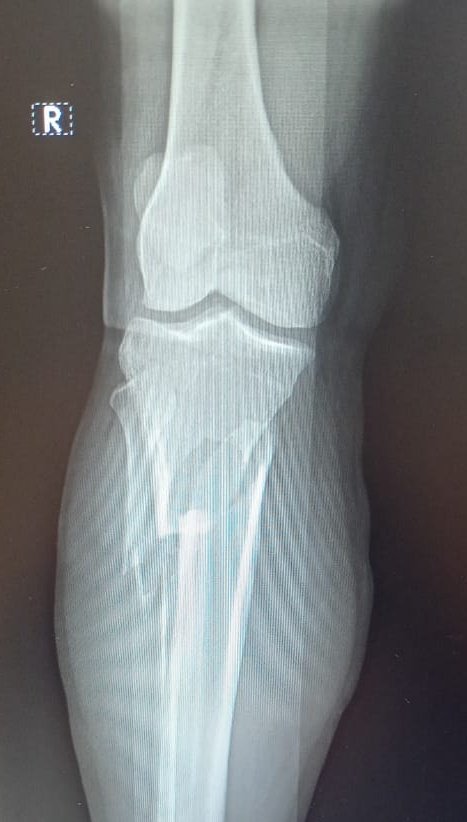

VAGA GENERAL🏥